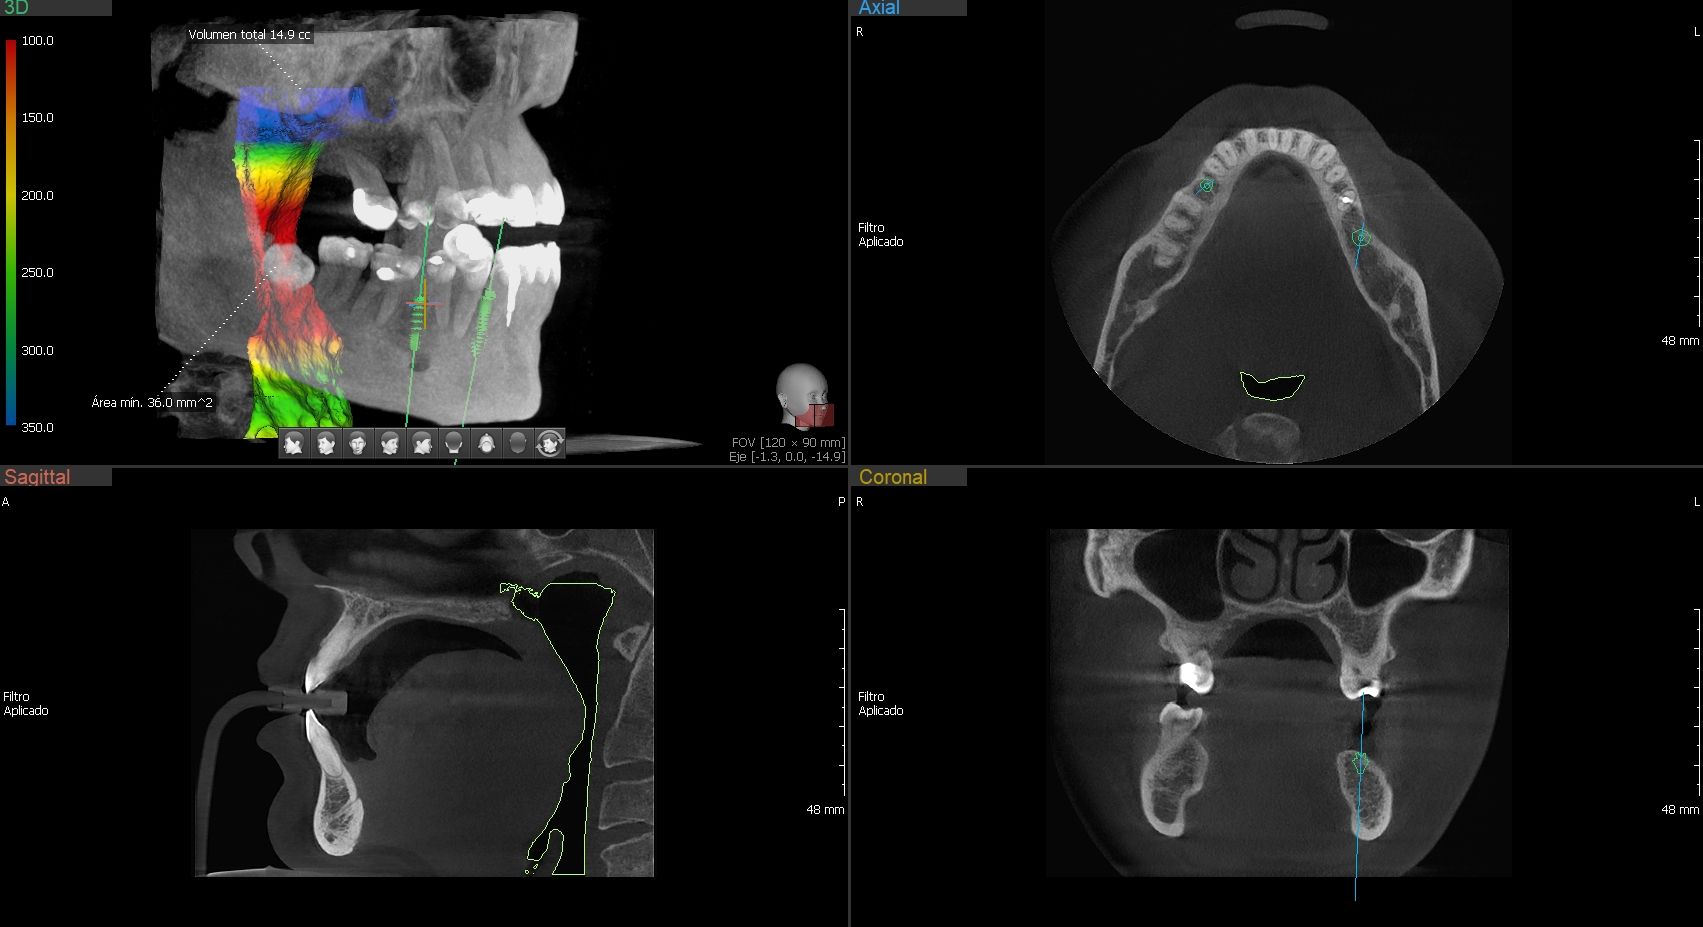

Green 16/18 ofrece una gama de campos de visión seleccionables. Multi FOV permite al usuario seleccionar el modo FOV óptimo y minimizar la exposición a áreas que no son la región de interés. Seleccione el tamaño adecuado de FOV entre 16×9/18×10, 12×9/13×10, 8×9 y 5×5 basado en una particular necesidad de diagnóstico. Cubre la región del arco completo, seno y la ATM izquierda / derecha y es adecuado para la mayoría de los casos de cirugía oral así como la cirugía de implantes múltiples. También puede medir el volumen de la vía aérea.